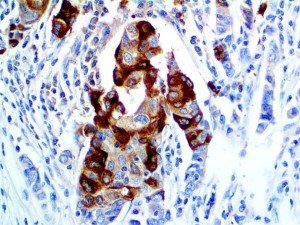

It is the ICU physician who is most likely to witness one of the deadliest manifestations of the abnormal immunological response, the cytokine storm syndrome (CSS). This response is also referred to by some as the cytokine release syndrome (CRS). CSS is characterized by continuous activation and expansion of macrophage and lymphocyte populations, which secrete large amounts of cytokines, causing the cytokine storm. This massive cytokine release is akin to hemophagocytic lymphohistiocytosis (HLH) disease, a syndrome characterized by initial unchecked and persistent activation of cytotoxic T lymphocytes and NK cells.